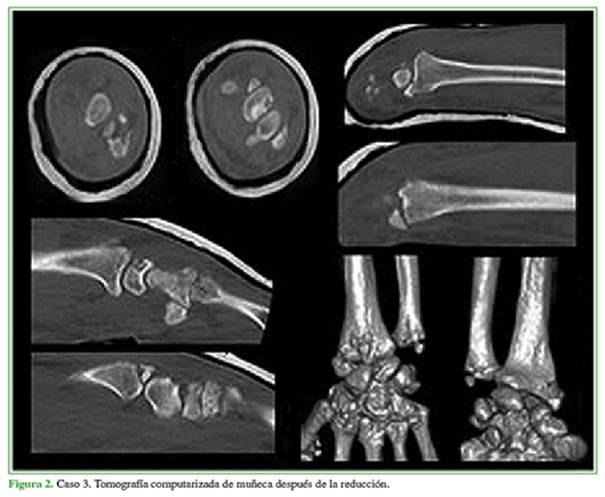

Se analizaron las lesiones de cada paciente y se formaron dos grupos diferenciados según la clasificación de Dumontier (Tabla 2). Se practicó una reducción cerrada en la sala de emergencia bajo anestesia local mediante tracción axial y desviación dorsal/palmar según la luxación e inmovilización con yeso braquipalmar. Posteriormente, se solicitó una tomografía computarizada (Figura 2) de cortes finos, axiales, coronales y sagitales con reconstrucción 3D para la planificación quirúrgica. Si las fracturas eran expuestas, se las trató dentro de las tres horas de producidas bajo el protocolo infectológico del hospital según la clasificación de Gustillo-Anderson. A los pacientes con exposición tipo I, se les administró cefalotina por vía intravenosa, durante 24 h, y a aquellos con exposición tipos II y III, clindamicina más gentamicina por 72 h, además de una limpieza quirúrgica.

Con relación a la técnica quirúrgica, en su gran mayoría, este tipo de lesiones requiere de una osteosíntesis de la estiloides radial, reanclado de la cápsula articular y sutura ligamentaria (radiosemilunar corto). Se utilizó el abordaje de Henry para radio distal (Figura 3). No fueron necesarios abordajes dorsales debido a la correcta reducción indirecta de los fragmentos fracturarios. La estabilidad/reducción fue controlada mediante radioscopia dinámica en el quirófano (Figura 4).